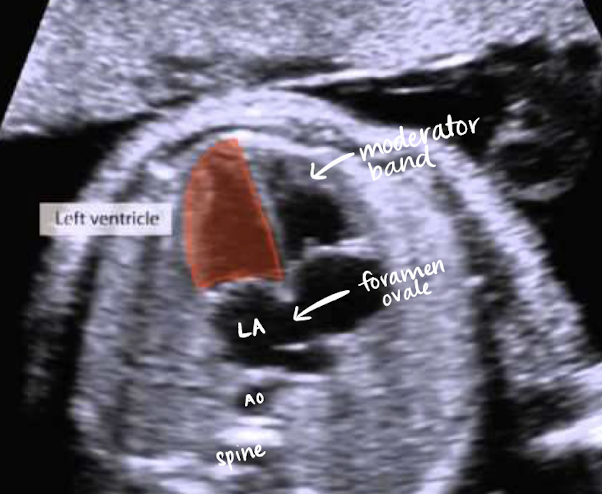

RV (right ventricle)

receives deoxygenated blood from RA

has a moderator band within it

normal: sends deoxygenated blood out through the main pulmonary artery to the lungs

fetus: blood gets shunted away from lungs by ductus arteriosus that connects MPA to AO)

ductus arteriosus connects MPA to AO—this allows blood to skip the lungs and go directly into systemic circulation

foramen ovale

opening between RA and LA

oxygenated blood bypasses fetal lungs

alows oxygenated blood from placenta (mother) to pass directly into LA

foramen ovale opens between RA and LA